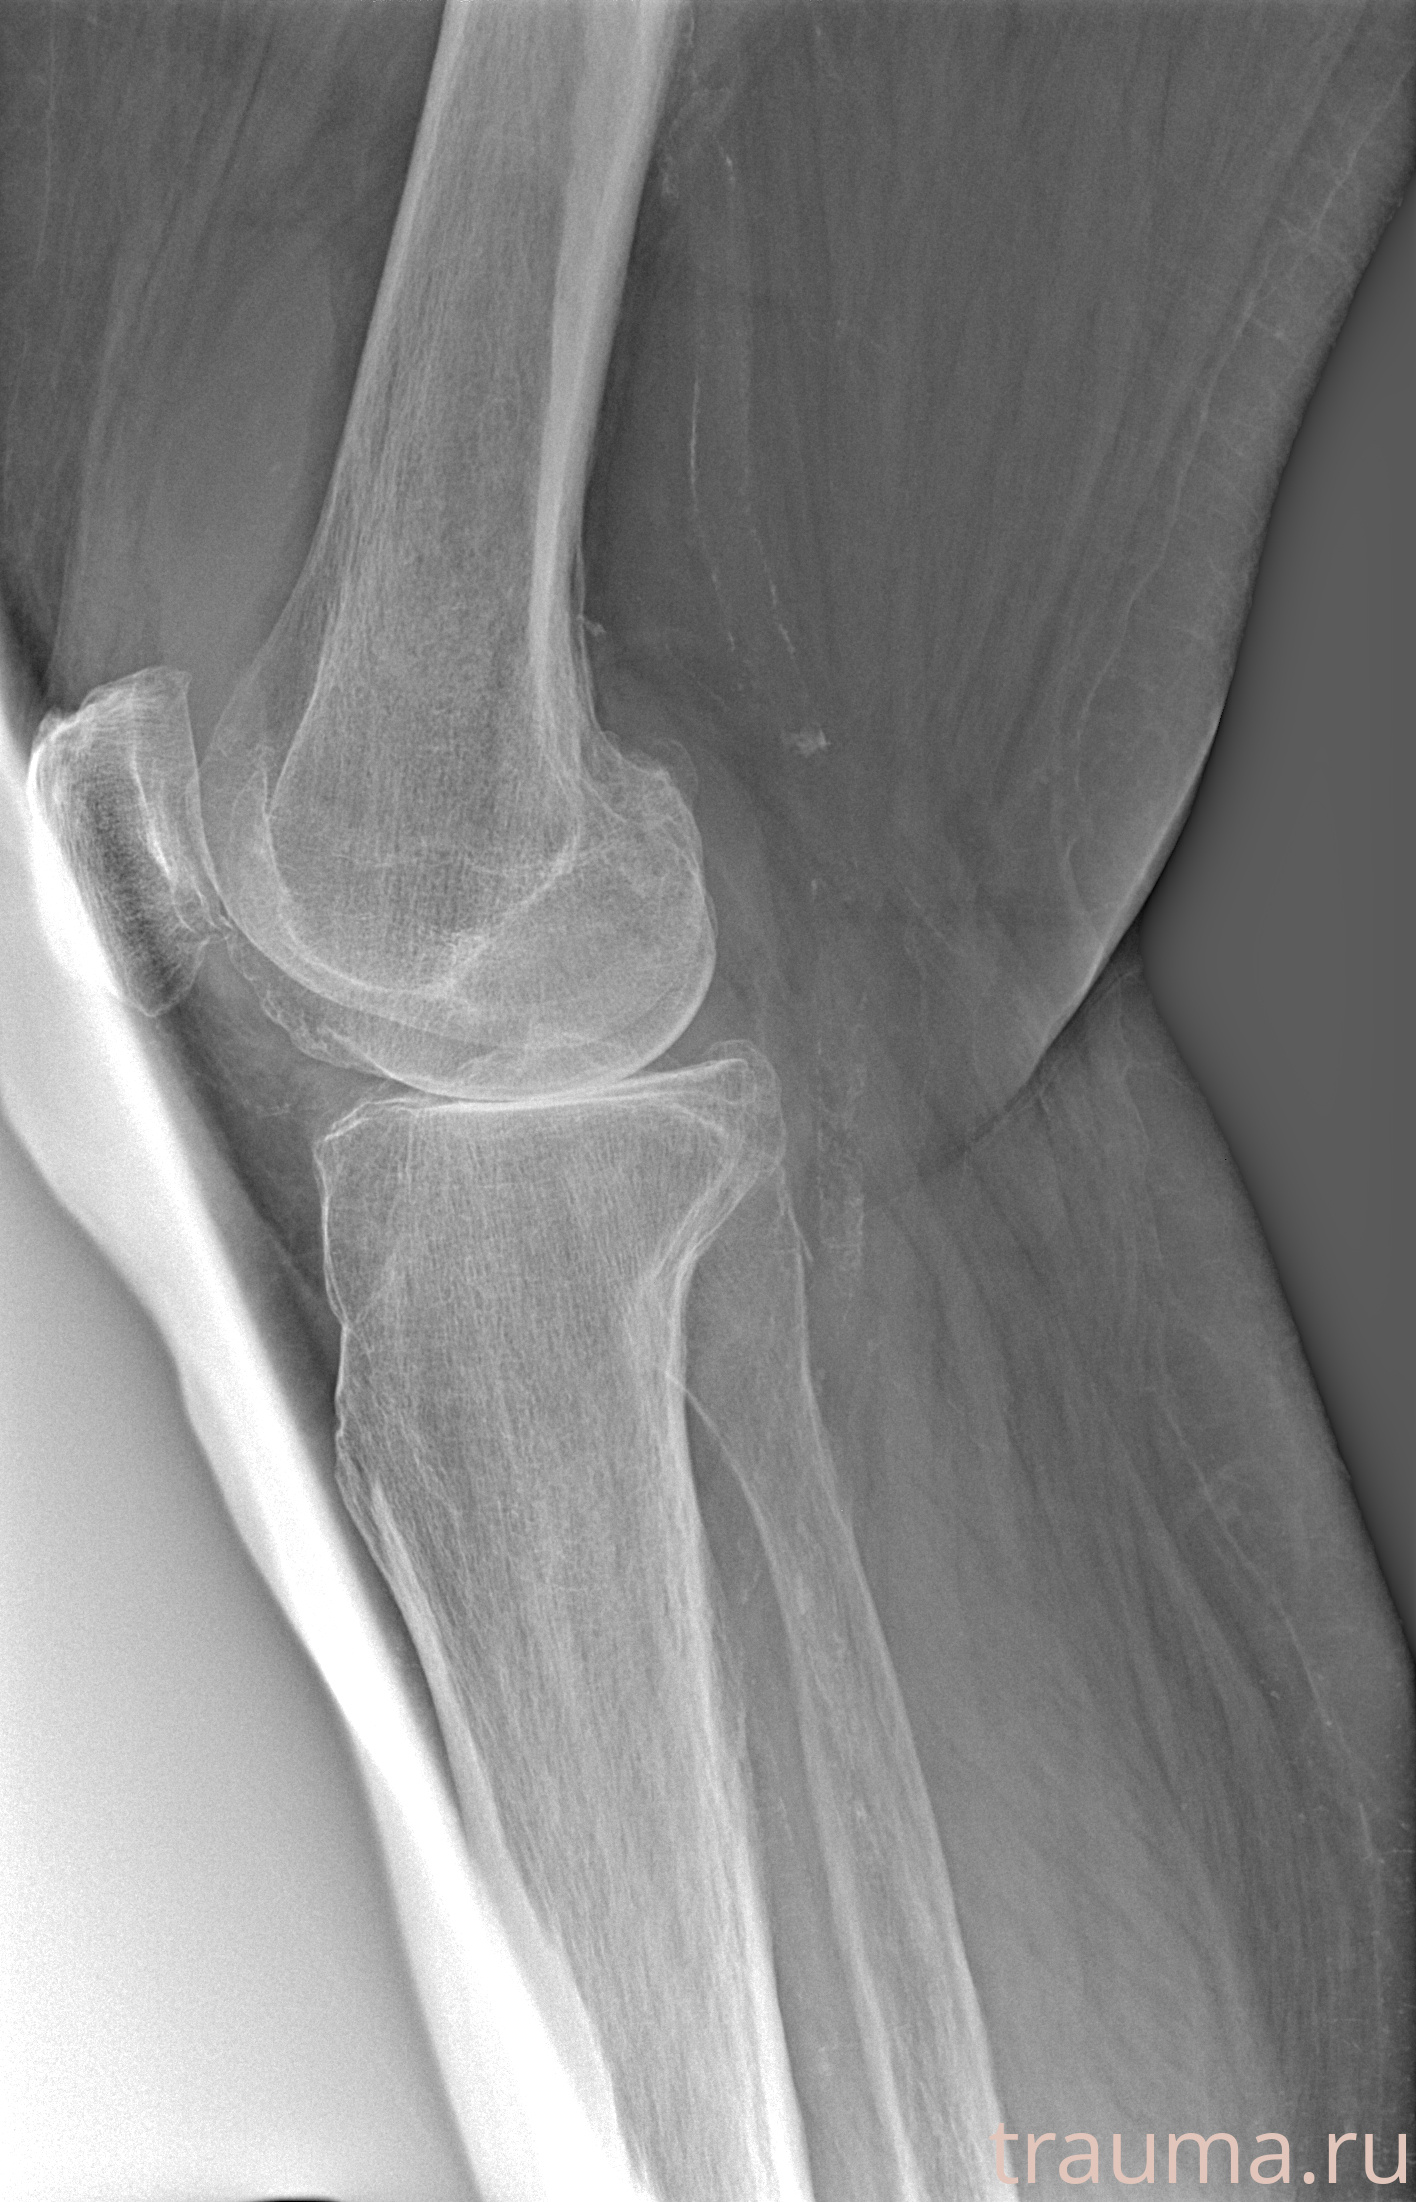

Рентгенограммы

Рентген на дому: по вашему адресу приезжает врач-рентгенолог, травматолог-ортопед с мобильным рентгеновским аппаратом, проводит диагностику травмы или заболевания, делает необходимые рентгенограммы, дает рекомендации по дальнейшему лечению. Получить качественные снимки в домашних условиях возможно благодаря уникальной методике, разработанной МосРентген Центром для института  Склифосовского